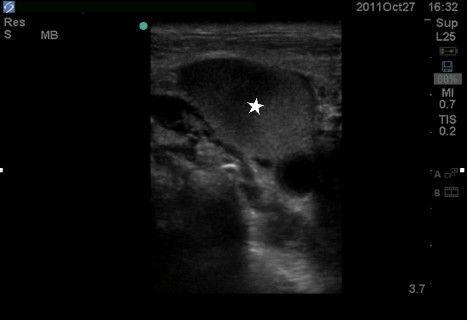

Superior vena cava (SVC) syndrome is most commonly the insidious result of decreased vascular flow through the SVC due to malignancy, spontaneous thrombus, infections, and iatrogenic etiologies. Clinical suspicion usually leads to computed tomography to confirm the diagnosis. However, when a patient in respiratory distress requires emergent airway management, travel outside the emergency department is not ideal. With the growing implementation of point-of-care ultrasound (POCUS), clinicians may make critical diagnoses rapidly and safely. We present a case of SVC syndrome due to extensive thrombosis of the deep venous system cephalad to the SVC diagnosed by POCUS.

上腔静脉(SVC)综合征最常见的原因是由于恶性肿瘤、自发性血栓形成、感染和医源性病因导致通过上腔静脉的血流减少而隐匿性产生的。临床怀疑通常会通过计算机断层扫描来确诊。然而,当呼吸窘迫的患者需要紧急气道管理时,离开急诊科去做检查并不理想。随着床旁超声(POCUS)的应用越来越广泛,临床医生可以快速、安全地做出关键诊断。我们报告一例因上腔静脉上方深静脉系统广泛血栓形成导致的上腔静脉综合征,该病例通过床旁超声确诊。